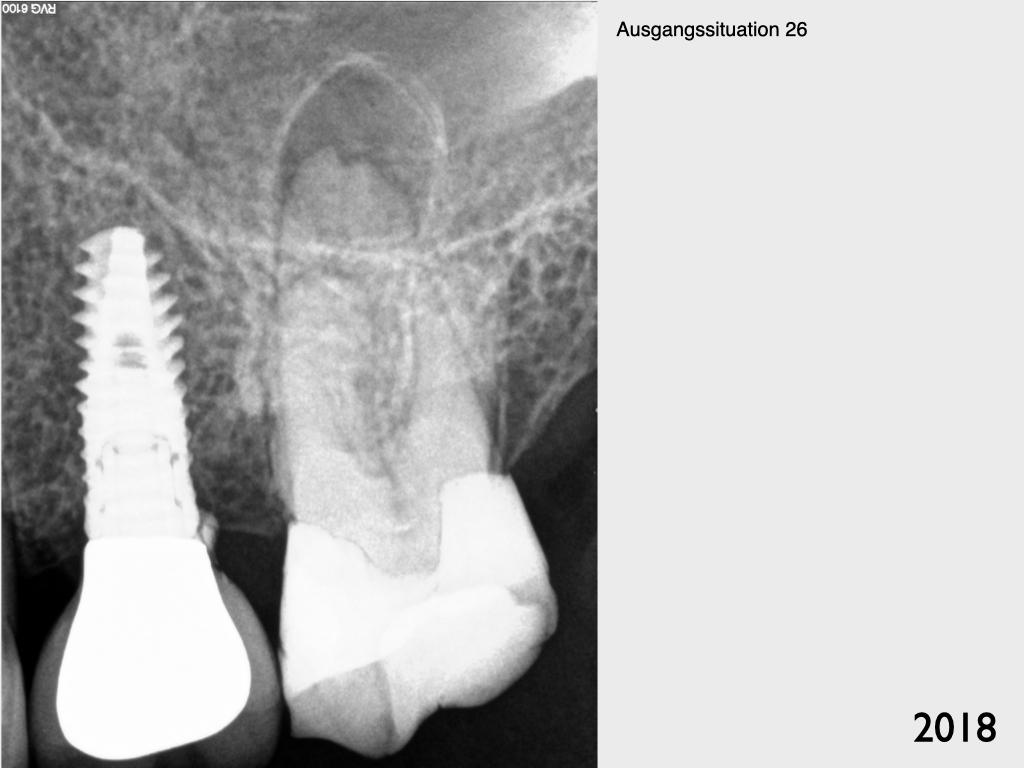

Implantat vs. Molar